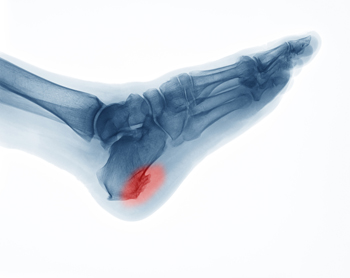

A heel spur can produce severe pain and discomfort, despite their small size. It is defined as a bony growth that forms on the bottom of the heel, generally as a result of consistent pressure the heel endures. Pain that often accompanies this condition is caused by an inflamed ligament that connects the heel to the toes, causing difficulty in completing daily tasks. This can happen from being obese, frequently running, or possibly from wearing shoes that do not fit correctly. Larger heel spurs may feel like a small hook on the inside of the heel that can be an inch or longer. Intense heel pain will often bring the patient to a podiatrist to have an X-ray taken, which can determine the exact size of it, although the pain is typically caused by inflammation. At the first sign of heel pain, it is strongly urged that you speak with a podiatrist who can offer treatment methods that are correct for you, which may include surgery for removal.

Heel spurs are formed by calcium deposits on the back of the foot where the heel is. This can also be caused by small fragments of bone breaking off one section of the foot, attaching onto the back of the foot. Heel spurs can also be bone growth on the back of the foot and may grow in the direction of the arch of the foot.

Older individuals usually suffer from heel spurs and pain sometimes intensifies with age. One of the main condition's spurs are related to is plantar fasciitis.

The pain associated with spurs is often because of weight placed on the feet. When someone is walking, their entire weight is concentrated on the feet. Bone spurs then have the tendency to affect other bones and tissues around the foot. As the pain continues, the feet will become tender and sensitive over time.